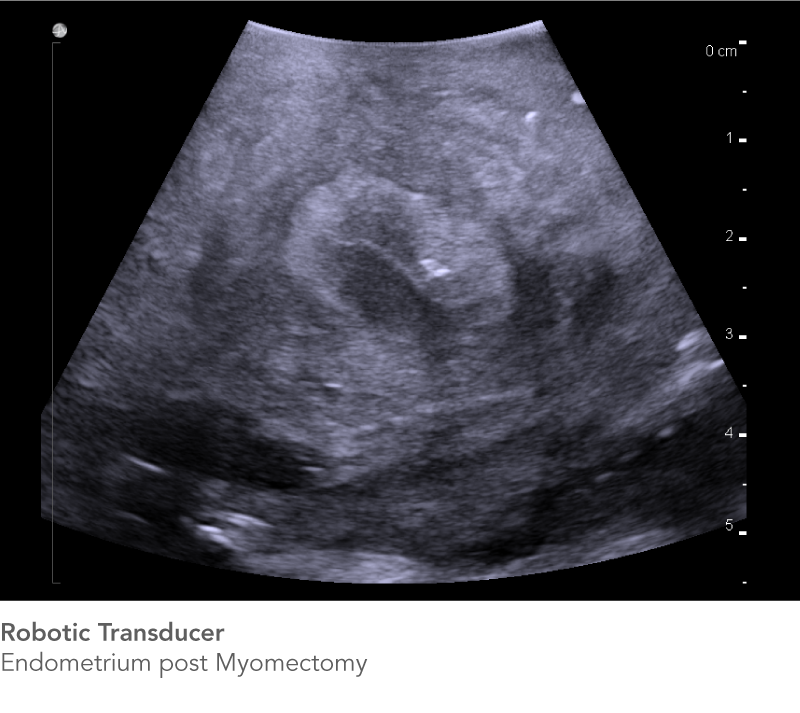

Robotic-Assisted Surgery

The bk5000 and bkActiv ultrasound systems and the Rob12C4 Robotic Transducer allow you to easily reach and clearly see regions of interest to achieve the best outcomes for your patients.

The Rob12C4 Robotic Transducer does more than Partial Nephrectomy. The high-resolution ultrasound transducer is designed to support robotics programs in a variety of procedures.